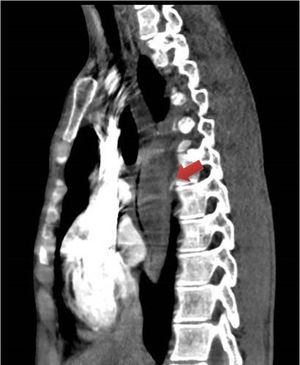

A 20-year-old man presented with chest pain and fever. Computed tomography of the chest showed a fusiform paravertebral mass measuring 27 × 30 × 100 mm indicative of a superinfected collection (Fig. 1). An oesophageal transit study with Gastrografin® ruled out perforation (Fig. 2). A decision was made to administer antibiotic therapy and perform a surgical examination given the evidence of superinfection. Intraoperative oesophagogastroduodenoscopy revealed, 30−36 cm from the dental arch, whitish oesophageal mucosa with haemorrhagic suffusion, a mass effect and two orifices draining a purulent fluid (Fig. 3). Right lateral thoracoscopy revealed thickening of the oesophageal wall, with no evidence of cyst formation. On subsequent imaging tests, the collection was seen to gradually shrink and then disappear. Oesophageal biopsies in follow-up oesophagogastroduodenoscopy yielded no histological findings.